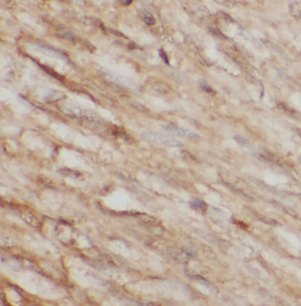

| 验证图片 | Immunohistochemistry of paraffin-embedded human stomach cancer tissue slide using FNab04823(LOX Antibody) at dilution of 1:200 heat mediated antigen retrieved with Tris-EDTA buffer(pH9). Jurkat cells were subjected to SDS PAGE followed by western blot with FNab04823(LOX antibody) at dilution of 1:600 |